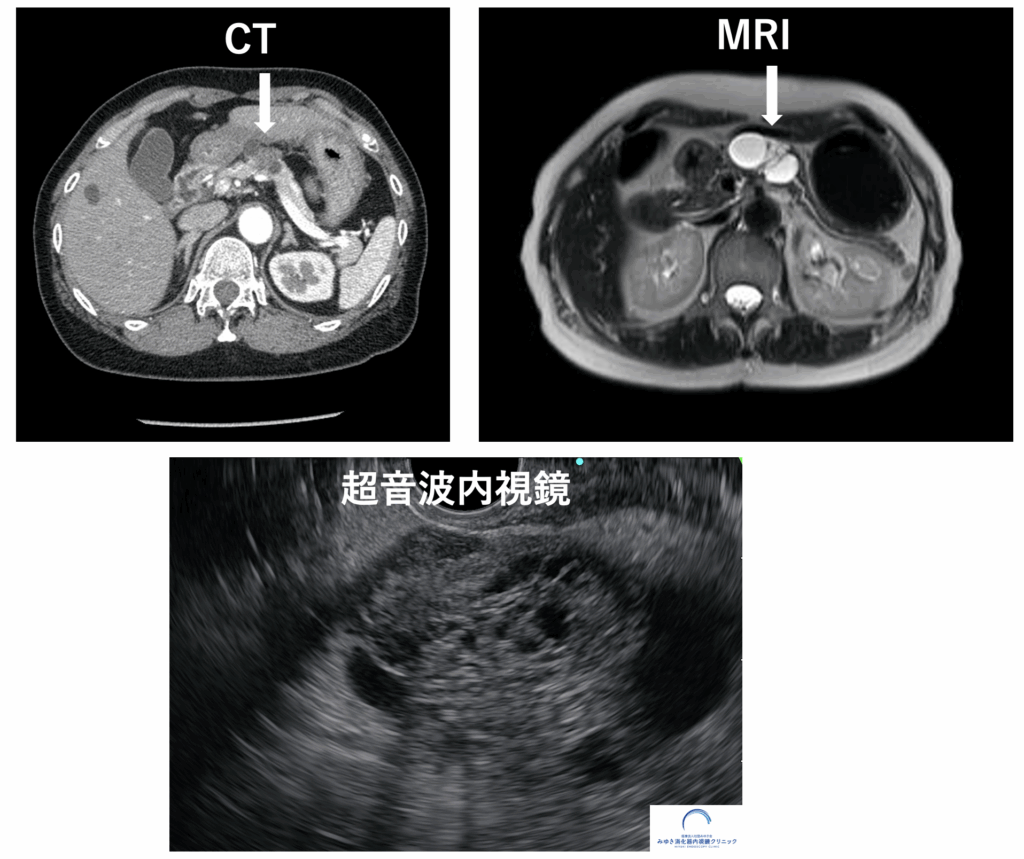

<膵しょう液性嚢胞腫瘍(SCN)>

CTやMRIの画像と比べて、超音波内視鏡検査では腫瘍内部の構造が詳細に観察できます

EUSはCTやMRIと比べて空間分解能(画像の細かさを示す指標)が非常に高く、わずか数mmほどの小さな腫瘍や膵嚢胞(すいのうほう)、早期の膵がんといった微細な異常も捉えることができます。他の検査で「異常なし」とされた場合でも、EUSによって初めて小さな病変が見つかることもあります。